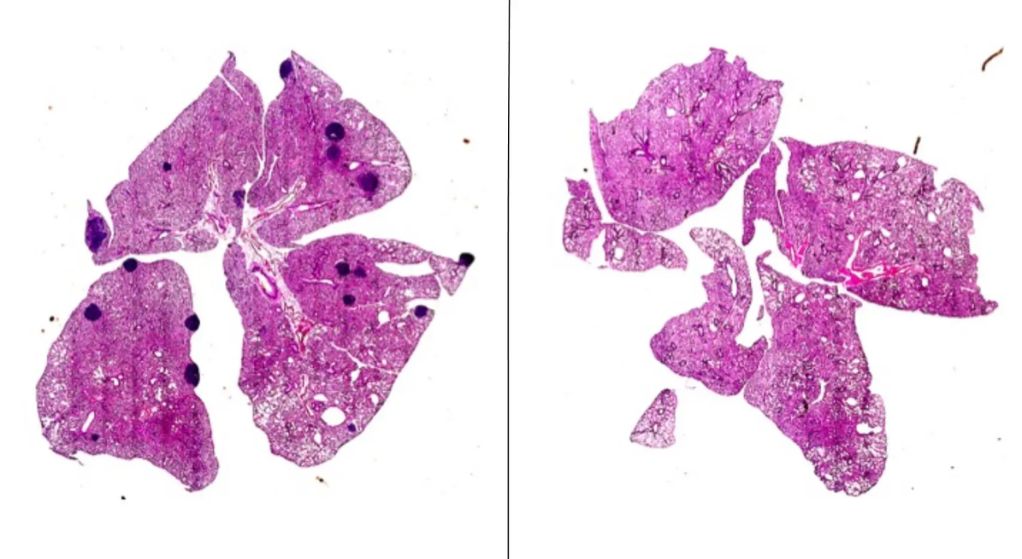

Aspirin, a new ally against cancer: metastasis is stopped in a novel experiment with mice

This common drug can prevent T cells from being inhibited, improving their ability to destroy cancer cells. Ángel Lanas, scientific director of the IIS Aragón, explains this to Science Media Centre.